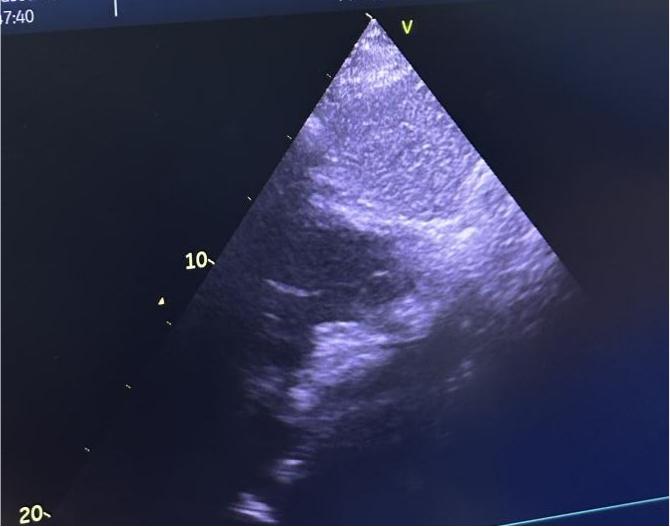

术后超声

手术在局部麻醉下进行,通过股静脉穿刺建立介入通道,在超声及X线引导下,将可降解封堵器精准输送至房间隔缺损处。封堵器展开后完全覆盖缺损部位,即刻超声显示分流消失,三尖瓣反流显著减少,手术全程耗时约1小时。术后患儿生命体征平稳,无不适症状,次日即可下床活动。其家属对治疗效果表示高度认可:“孩子终于能像其他同龄人一样正常上学,上体育课了,感谢宋主任团队!”